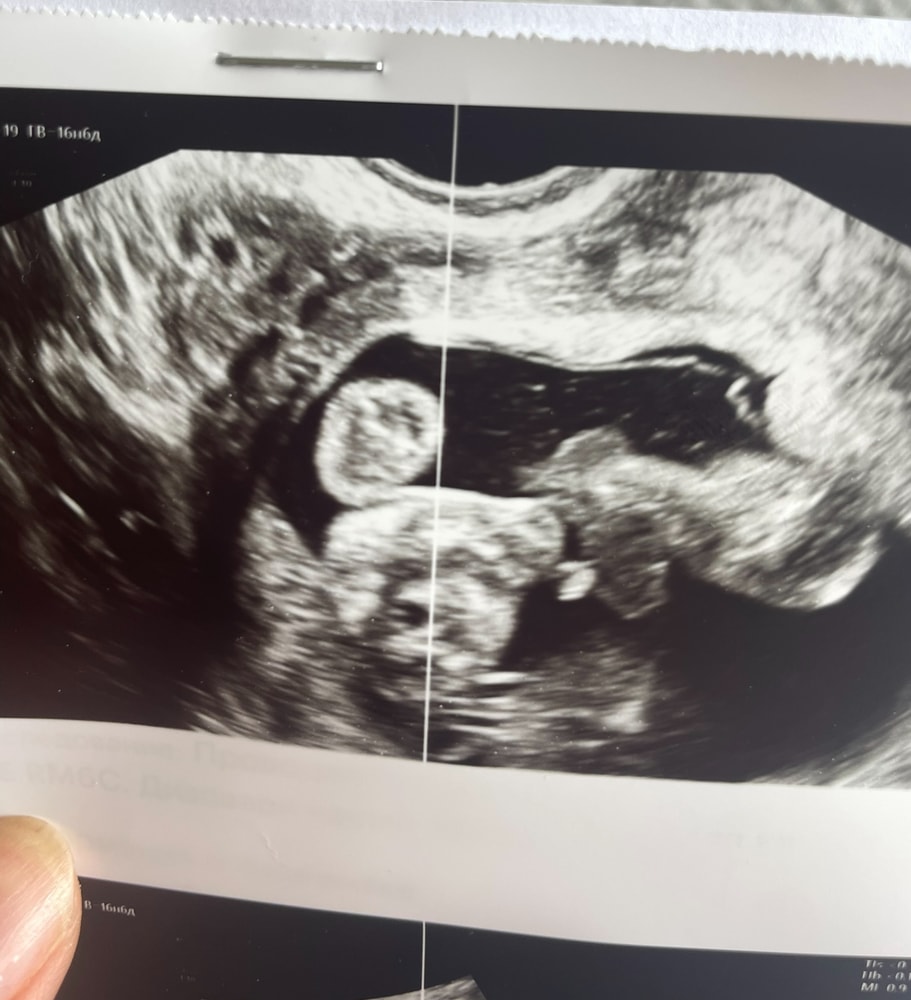

Мальчик или девочка в 16 недель и 6 дней.

Ничего не пойму, что за ракурс

Маргарита , Где я обвела кружочком, врач сказала, что это похоже на мошонку Изображение

Светлана , это вообще какие части тела зафотали? Реально не понятно и это точно не мошонка

До второго скрининга даже врачи точно сказать не могут. Плохо еще видно. Ложитесь второго скрининга и все Вам точно скажут😊

Зачем гадать, если даже врач не сказал пол точно. На 2ом скрининге может скажут